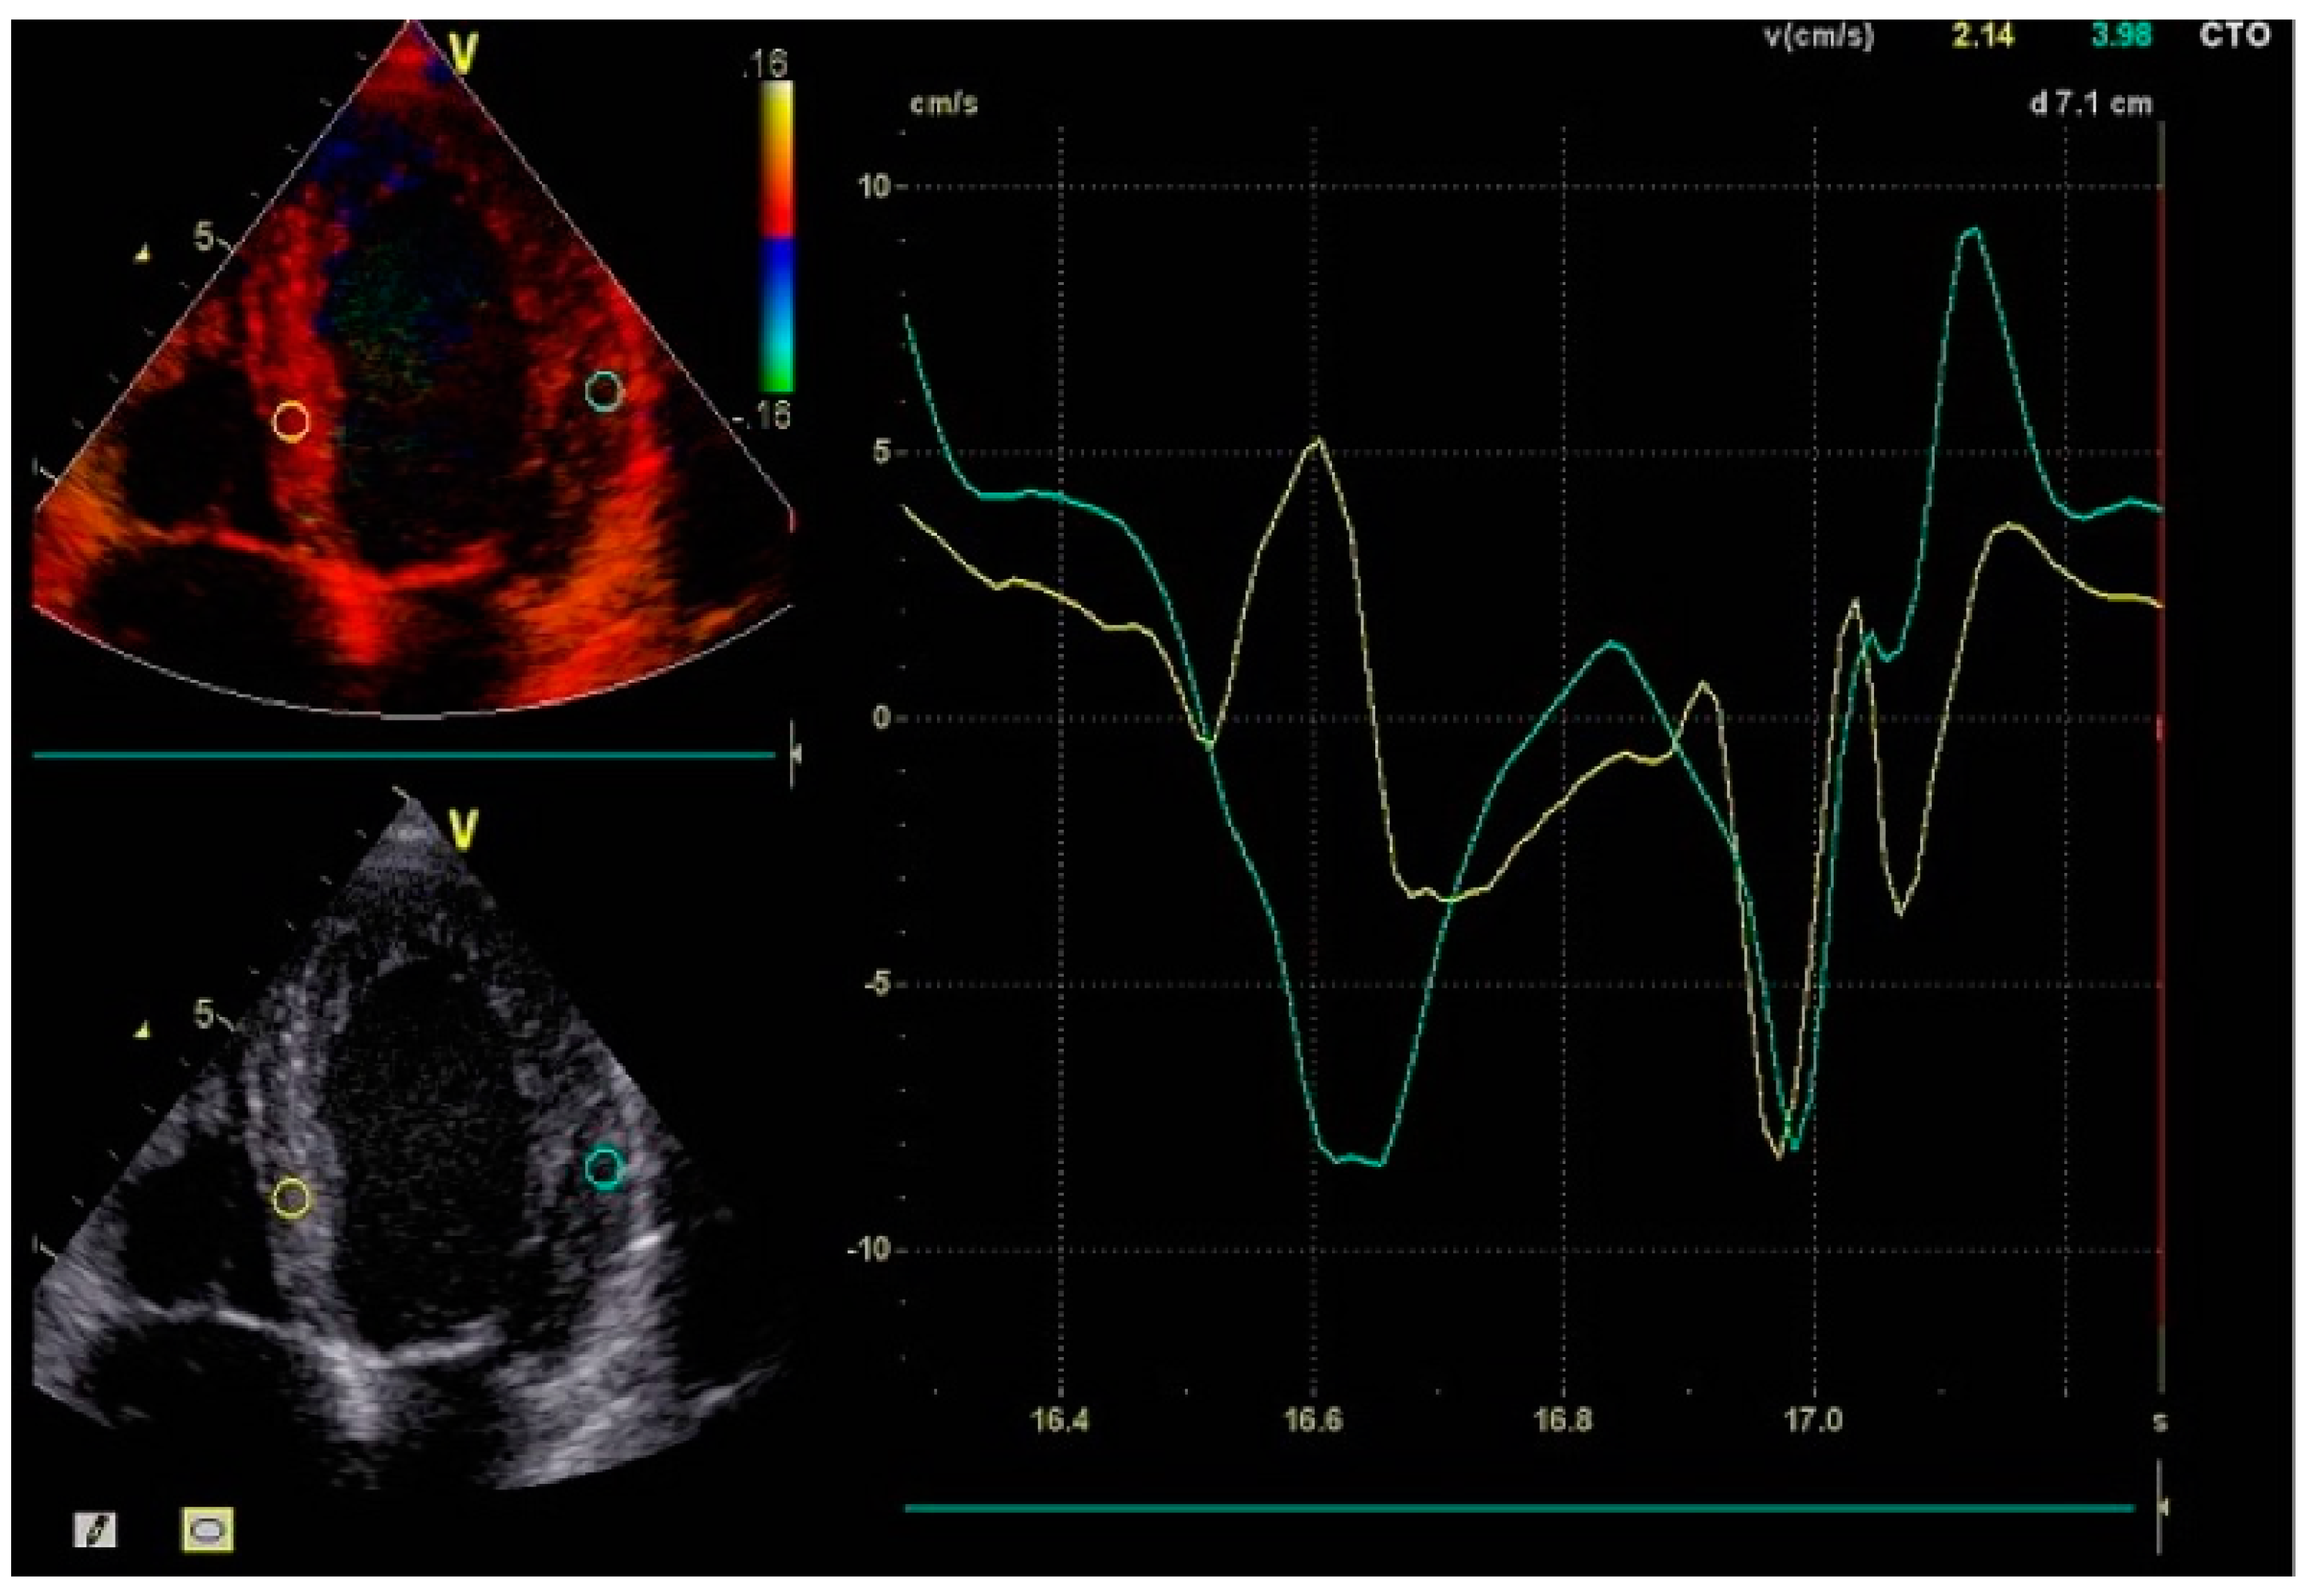

Although a QRS duration of ≥130 milliseconds on electrocardiography is a key criterion for BBP suitability [16], echocardiographic advancements have greatly enhanced the assessment of ventricular mechanics and their response to treatment in patients with LBBB and HFrEF. Imaging plays a pivotal role in guiding patient selection for BBP or CRT, predicting treatment response, and monitoring the long-term success of resynchronization therapy [17]. The ability to detect subtle changes in myocardial mechanics, such as GLS improvements or reductions in septal-to-lateral delay, allows for individualized therapy optimization, ultimately improving patient outcomes [18] (Figure 5).

Speckle-Tracking Echocardiography: STE provides a refined evaluation of myocardial deformation by analyzing strain and strain rate. Unlike TDI, which measures myocardial velocities, STE evaluates the percentage change in myocardial length during contraction, offering a more precise assessment of ventricular mechanics [20].

In LBBB, GLS is often significantly reduced due to asynchronous myocardial contraction. STE generates strain maps illustrating areas of delayed or paradoxical motion. The interventricular septum typically exhibits reduced or negative strain in early systole, while the lateral wall demonstrates delayed peak strain, underscoring the extent of dyssynchrony [21]. This quantitative analysis aids in determining a patient’s likelihood of responding to resynchronization therapy.

STE has several advantages over TDI, including angle independence and greater accuracy in detecting subclinical LV dysfunction. Improvements in GLS following BBP or CRT are strongly correlated with better clinical outcomes, including enhanced LVEF, reduced ventricular volumes, and improved functional capacity [22].

Figure 5. Speckle-tracking echocardiography showing global longitudinal strain analysis. The strain curves indicate significant dyssynchrony, and the bullseye plot reveals severely impaired GLS, suggesting advanced myocardial dysfunction.